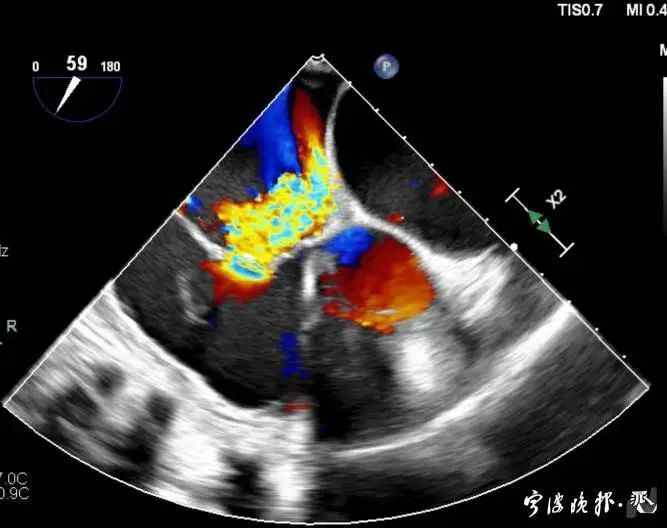

術(shù)前食道心超示三尖瓣重度反流

得知可以微創(chuàng)手術(shù),陳大爺一家決定放手一搏。寧波市醫(yī)療中心李惠利醫(yī)院心臟瓣膜中心團(tuán)隊(duì)反復(fù)就術(shù)前準(zhǔn)備、手術(shù)步驟及術(shù)后可能出現(xiàn)的各種情況做了預(yù)案。3月4日,陳大爺?shù)氖中g(shù)成功進(jìn)行,術(shù)中得到LuX-Valve經(jīng)導(dǎo)管三尖瓣置換術(shù)原創(chuàng)團(tuán)隊(duì),上海長海醫(yī)院陸方林主任團(tuán)隊(duì)的鼎力支持,術(shù)后陳大爺?shù)男呐K三尖瓣反流立即消失。術(shù)后瓣膜中心CCU(心臟監(jiān)護(hù))團(tuán)隊(duì)和心內(nèi)科團(tuán)隊(duì)迎接一個(gè)又一個(gè)右心瓣膜置換后的血流動力學(xué)改變等帶來的挑戰(zhàn),克服種種難關(guān),二周后患者進(jìn)入早期心臟康復(fù)。目前陳大爺已經(jīng)順利出院,沒有胸悶氣急,生活自理,精神狀態(tài)也很好,瓣膜中心團(tuán)隊(duì)也在對他持續(xù)隨訪中。